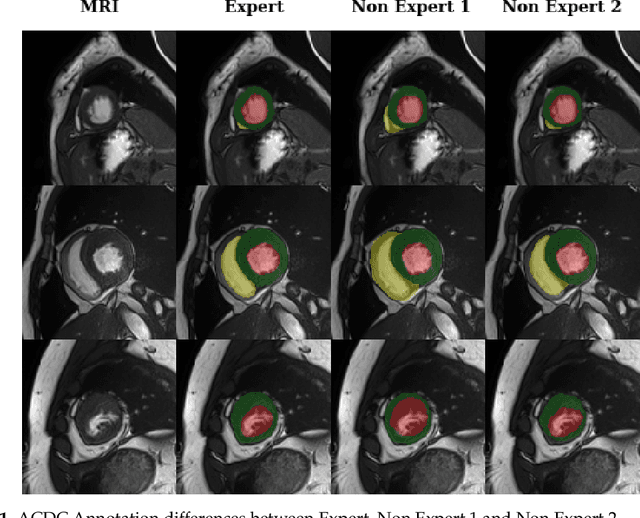

Deep learning methods are the de-facto solutions to a multitude of medical image analysis tasks. Cardiac MRI segmentation is one such application which, like many others, requires a large number of annotated data so a trained network can generalize well. Unfortunately, the process of having a large number of manually curated images by medical experts is both slow and utterly expensive. In this paper, we set out to explore whether expert knowledge is a strict requirement for the creation of annotated datasets that machine learning can successfully train on. To do so, we gauged the performance of three segmentation models, namely U-Net, Attention U-Net, and ENet, trained with different loss functions on expert and non-expert groundtruth for cardiac cine-MRI segmentation. Evaluation was done with classic segmentation metrics (Dice index and Hausdorff distance) as well as clinical measurements, such as the ventricular ejection fractions and the myocardial mass. Results reveal that generalization performances of a segmentation neural network trained on non-expert groundtruth data is, to all practical purposes, as good as on expert groundtruth data, in particular when the non-expert gets a decent level of training, highlighting an opportunity for the efficient and cheap creation of annotations for cardiac datasets.